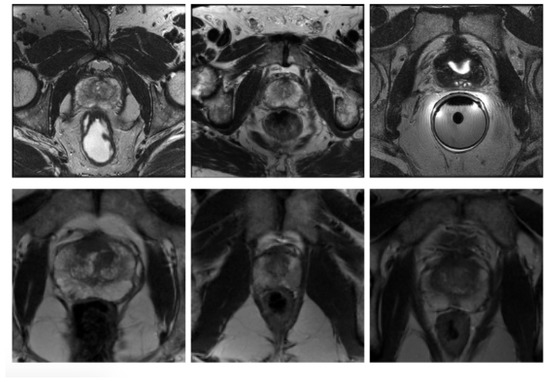

In order to examine the generalisability of the models on another representative set of MR images acquired in a clinical setting, the publicly available dataset (PROMISE12) [25] was used. This dataset contains 50 cases including T2-weighted MR images of the prostate. This dataset is multi-center and multi-vendor and has different acquisition protocols, with various prostate sizes and appearances. Details of the acquisition protocols for the different centers is explained by Litjens et al. [25]. Due to different MRI protocols (e.g., differences in slice thickness, magnet strength, with/without endorectal coil), the quality of the images was different in this cohort. Figure 2 shows some slices from different data cohorts to show appearance differences. There is a spread in prostate sizes and appearance in all images in our clinical cohort and the public dataset.

Figure 2.

Some slices from different data cohorts to show appearance differences with T2 modality. First row: PROMISE12 dataset. Second row: our clinically collected dataset.

In terms of the T2W modality, similar outcome was achieved with regards to the training samples used during learning procedure for the cGAN model. The combination of raw and GNA was the best in the cGAN model; while the combination of raw and SP obtained the best output results in the cycleGAN model. To justify this by investigating the T2W modality images, we observed that the images in this modality show anatomy, especially the peri-prostatic structures, more clearly than other modalities. Figure 6 shows that ADC and DWI images have low signal around the prostate compared to the T2W modality. Superpixelizing the T2W images groups the pixels better and makes the surrounding anatomy more visible for the cycleGAN network. In the cycleGAN model there are two different domains and there is no paired input-output relation between them. The generators are penalized by the adversarial loss with the cycle consistency loss, which forces the generators to not only do the segmentation but also synthesize the original MR image from the created mask back again. As a result, the network learns a mapping between the training images and their masks and vice versa. Therefore, for the SP approach, learning is more optimised. When we compare the results of the raw plus SP images on the three modalities in the cycleGAN model, it is also consistent with this result that training using the T2W modality images obtained the best results (with DSC values of 0.748) while the DSC outcomes for DWI and ADC modalities were 0.702 and 0.710, respectively. For the DWI modality, the best results for the cGAN and cycleGAN models were achieved by using the raw plus MM images as the training set. The MM approach removes the unnecessary details from an image helping the network to focus on prostate tissue as the target part of the image during the training process. It shows consistent results with regards to the three evaluation metrics. The ROC curves and AUC values for these networks, applied to three modalities (ADC, DWI and T2W), are shown in Figure 7.

Figure 6.

Some examples of T2W, ADC and DWI MR images from our dataset, which demonstrates that DWI and ADC modalities have lower signal around the prostate compared to the T2W modality. Scaled images are shown in Figure A2 for better visualisation.

Figure A2.

Some examples of T2W, ADC and DWI MR images from our dataset, which demonstrates that DWI and ADC modalities have lower signal around the prostate compared to the T2W modality.